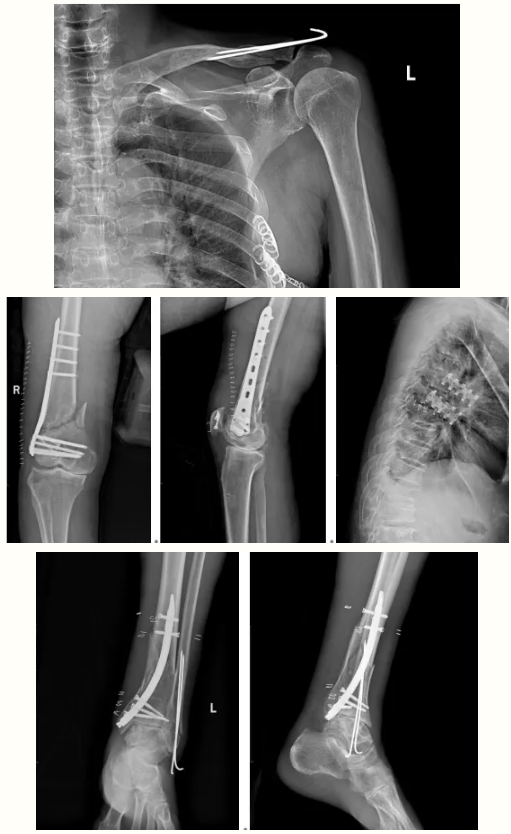

術(shù)前影像:

術(shù)后影像: